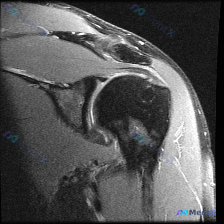

足跟MRI发现足底软组织积液,这几种鉴别容易漏!